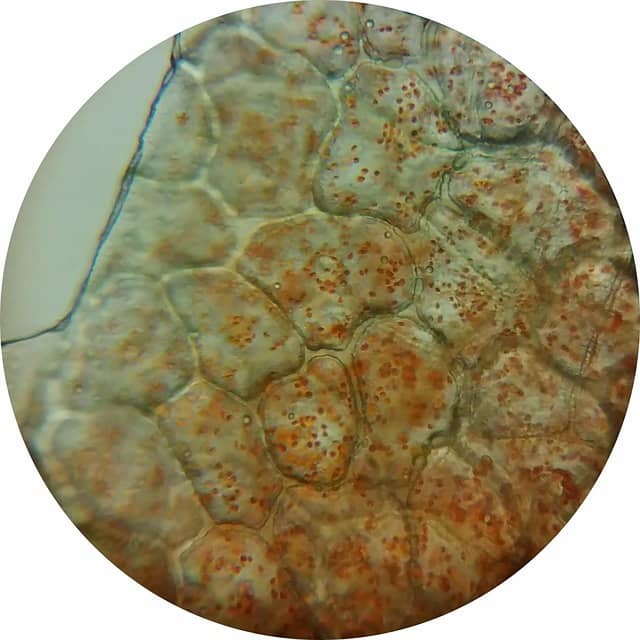

하이드로겔은 고분자 네트워크가 물을 다량 포함한 구조로,

상처 부위의 수분·온도·pH를 일정하게 유지해 세포 이동과 성장에 최적화된 환경을 제공합니다.